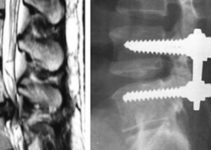

Це збірне поняття, яке об’єднує в собі більше десятка видів онкологічних захворювань лімфатичної системи. Від них страждають не тільки лімфовузли, але і всі органи і тканини, до складу яких входить лімфоїдна тканина. Це означає, що під загрозою опиняється кожна частина організму людини.

Неходжкінська хвороба може мати пасивну або повільно зростаючу форму, так і досить агресивну. Причини появи і розвитку досі невідомі науці, що істотно ускладнює процес лікування. Є припущення, що головний фактор розвитку — віруси. Часто лімфоми з’являються після операцій з трансплантації. У цей момент імунна система досить пригнічена, що ймовірно впливає на розвиток пухлини.